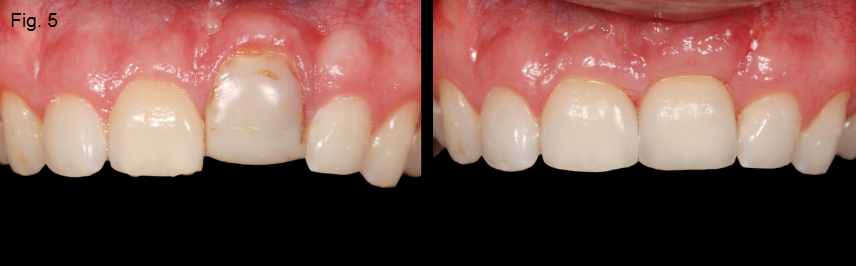

If the ankylosed tooth is an esthetic issue and the rate of the resorption is advancing quickly, extraction of the tooth is recommended. The area will typically require augmentation with either hard or soft tissue, depending if the final restoration is a single-tooth implant or a tooth-supported FPD (Figures 5 and 6).